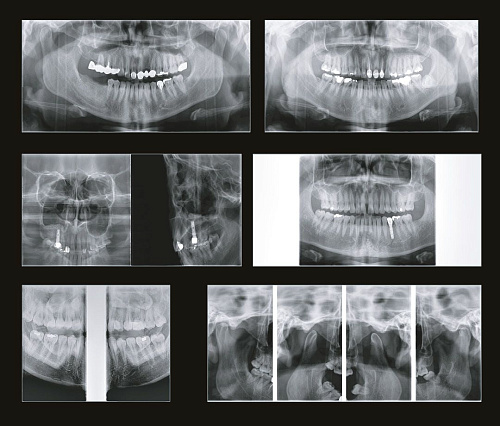

Аппарат базовой комплектации оснащается зоной сканирования 16×8 см. Имея аппарат с зоной сканирования 16×8 см возможно произвести несложный апгрейд для увеличения зоны сканирования до 16×14 см без замены аппарата.

Размеры исследований Genoray Volux 55_2.jpg

Простое и привычное ПО Triana

Программное обеспечение TRIANA обладает всем необходимым функционалом, необходимым для постановки диагноза и планирования лечения врачом-стоматологом.